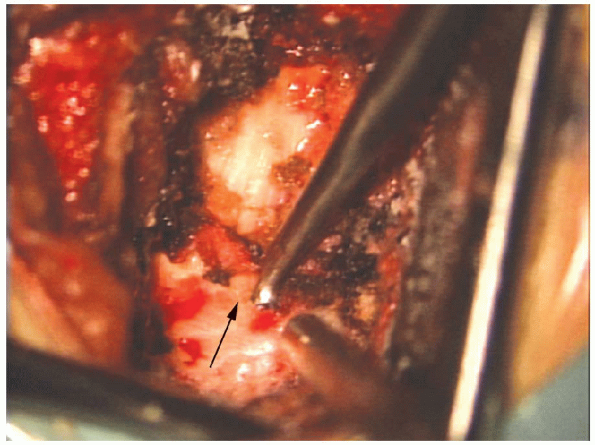

and removal of the herniated portion of the disc material (Fig. 17-25). A

single vertical incision is preferable to a rectangular annulotomy. A

thin, healed annular scar is probably a stronger barrier to recurrent

disc herniation than a broad fibrous scar over a large annulotomy.

The pituitaries and curettes allow for local, aggressive removal of

disc material from directly under the nerve root. Aggressive “radical”

discectomy of the entire disc space with scraping of the endplates is

not indicated. There is no evidence that this prevents recurrence or

promotes a spontaneous interbody fusion over the course of time.